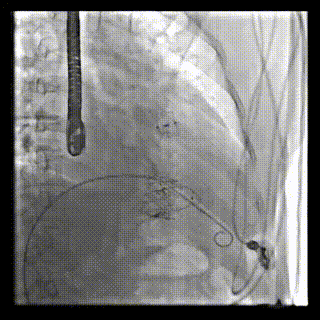

本周三例接受LuX-Valve Plus經(jīng)血管三尖瓣置換術(shù)的患者中,第一例患者為冠狀動脈旁路移植術(shù)+Bentall+二尖瓣成形術(shù)后;第二例患者為永久起搏器植入術(shù)后,存在跨三尖瓣導(dǎo)線;第三例患者合并房顫、房缺及左心耳封堵術(shù)后。

三例患者入院后,葛均波院士團隊周達新教授、潘文志教授、張源博士、陳莎莎博士及心超室的潘翠珍教授、李偉教授對患者的情況進行詳細評估和討論,最終決定為三例患者選擇LuX-Valve Plus40mm、50mm和50mm型號的瓣膜進行手術(shù)治療。手術(shù)后即刻拔除氣管插管,術(shù)后患者三尖瓣反流癥狀得到顯著改善,復(fù)查心超結(jié)果顯示人工三尖瓣瓣膜支架固定穩(wěn)定,瓣葉關(guān)閉形態(tài)未見異常,未見明顯反流。